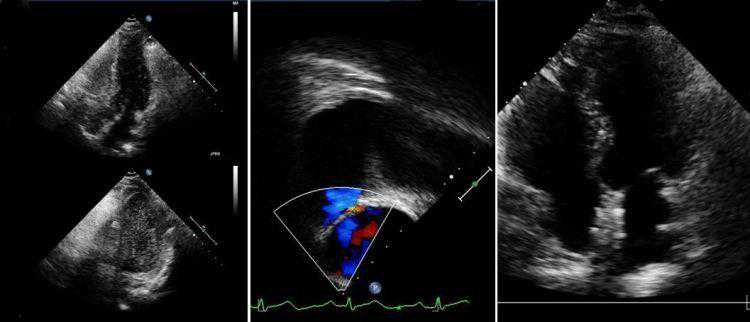

患者术前TCD发泡试验:静息状态(上)少量微泡信号,Valsalva动作后(下)可见大量微泡信号,形成“雨帘”。

患者术前经胸超声:静息状态(左上)可见少量微泡信号;Valsalva动作后(左下)可见大量微泡信。患者术前经食道超声(中):可见异常的“右向左分流”血流信号。患者术后经胸超声:(右)术后未再发现异常分流。